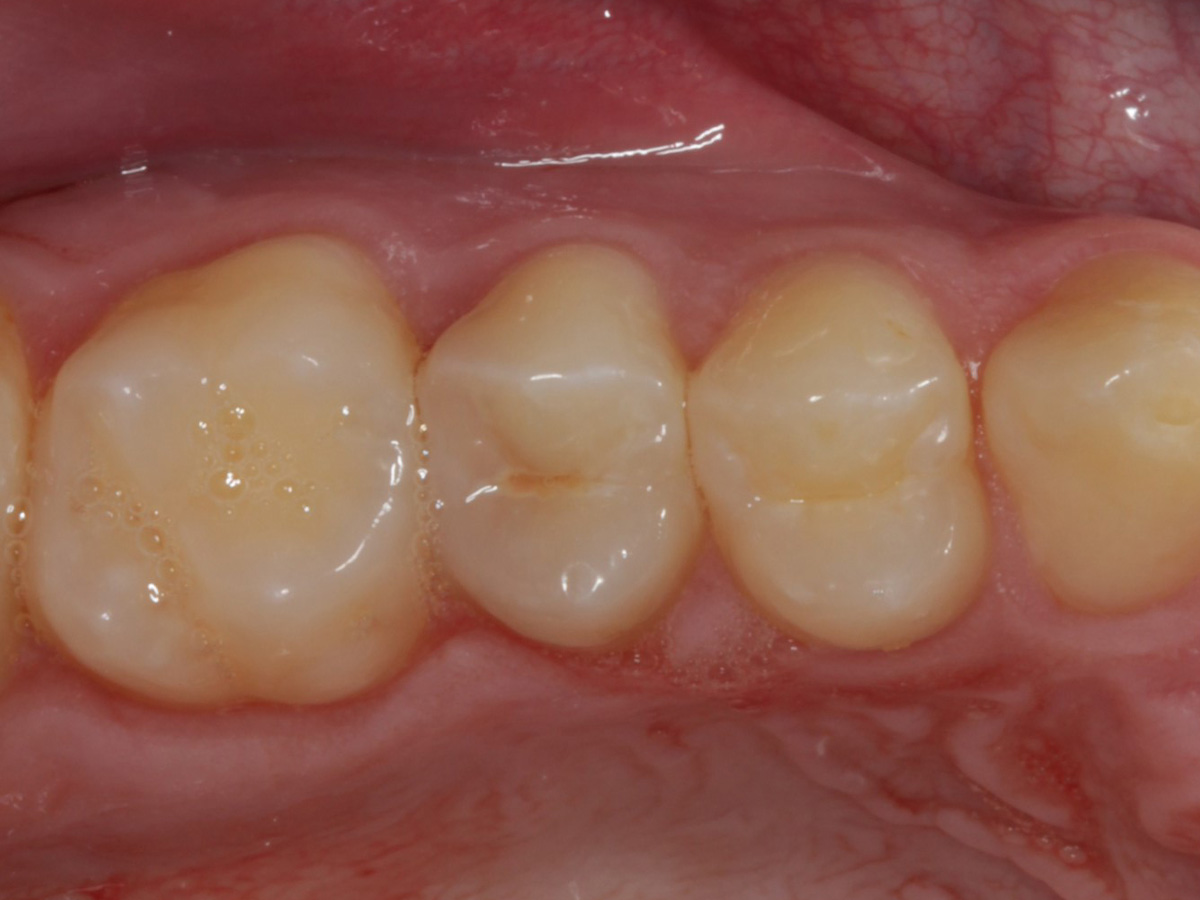

Abbildung 28

Kompositrestauration nach „Schachtverschluß“; keine Krone geplant

Abbildung 29